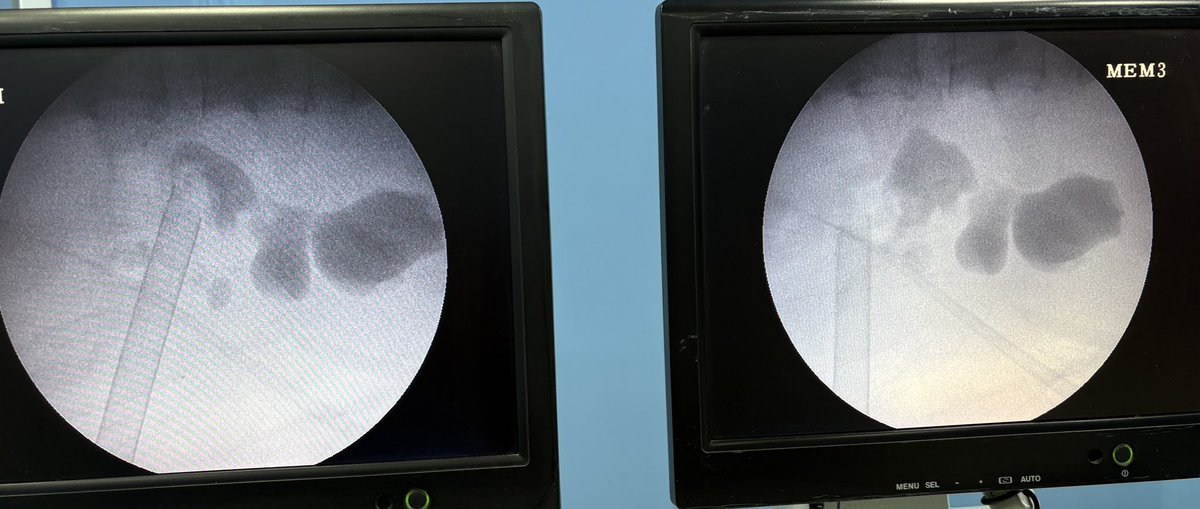

Large 30*25 mm partial staghorn calculus. HU 1400. Lithotripsy time 60 mins. Multiple calyx at acute angles and multiple horns are a difficult task. @ValdiviaUria @DrVCMohan @ValdiviaUria @StefaniaFerret @DrParimalGharia @GuidoGiusti @ArunkumarDr @dr_avreen @Mohamedendourol